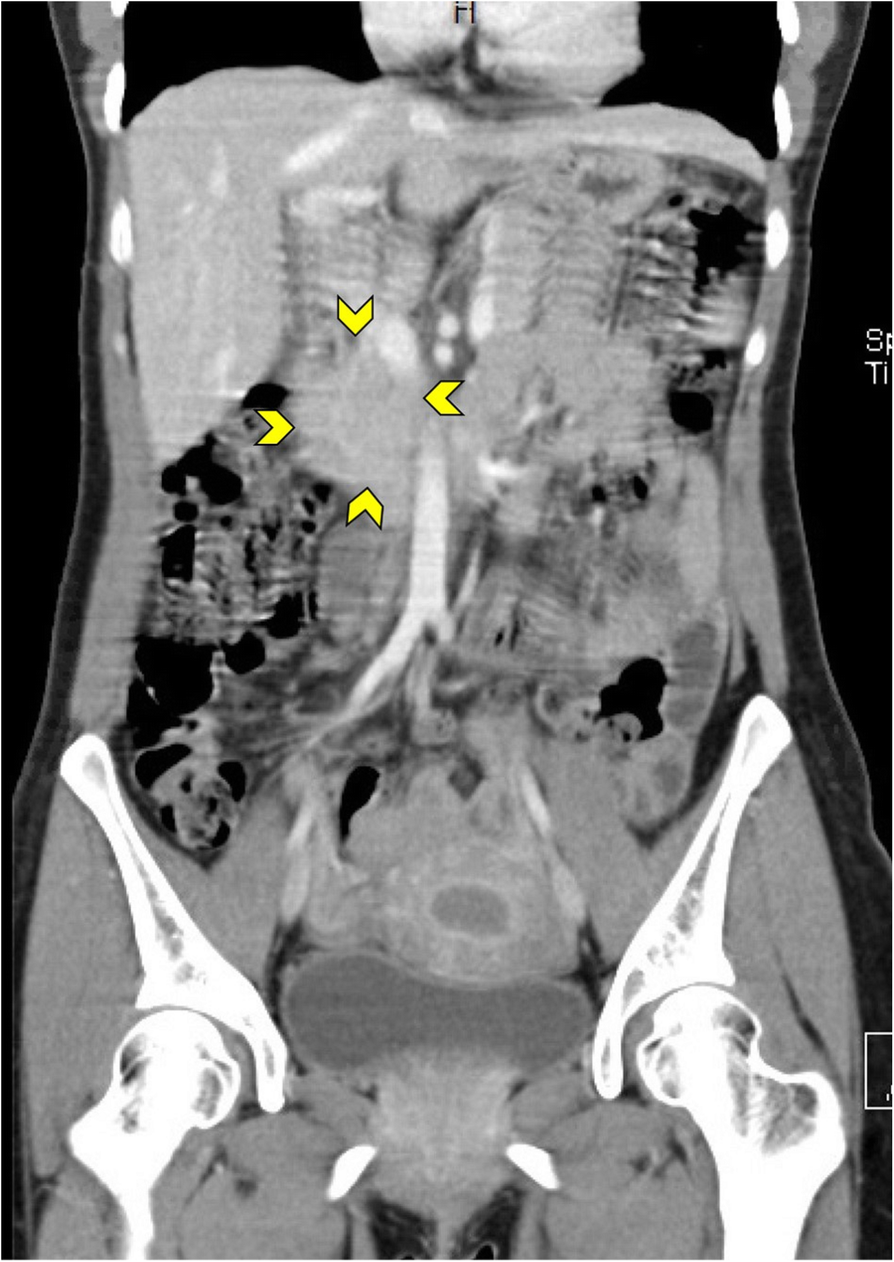

Fig. 2

A 29-year-old woman presented with epigastric and lower abdominal pain, fresh vaginal bleeding, and weight loss. Coronal CT scan of the abdomen with intravenous contrast revealed a non-enhanced complex mass lesion measures 4 × 2.5 cm anterior and to the right of the IVC at the level of L3-L4 vertebrae suggesting matted lymph nodes (arrows). Acid Fast Bacilli smear from the mass was positive